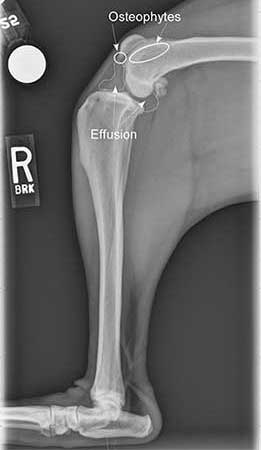

Radiographs (X-rays) provide additional information that can be helpful. It allows the veterinarian to see effusion (fluid) in the dog’s knee and bone spurs (osteophytes) around the knee, both of which indicate there is a problem in the knee. In some cases, one can also see that the femur (thigh bone) has slid backward on top of the tibia (shin bone), which does indicate CCL rupture. However, in cases of “partial CCL rupture,” there are times when both the physical exam and the radiographs are subtly abnormal. Since the CCL cannot be seen on an X-ray, the diagnosis is considered presumptive, or tentative, at this point.